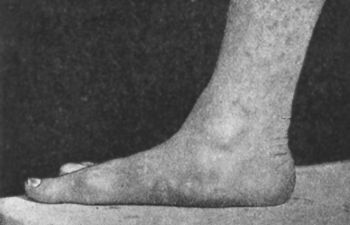

| 148. | Pes Calcaneo-valgus with excessive arching of Foot | 284 |

| 149. | Pes Calcaneo-valgus, the result of Poliomyelitis | 285 |

| 150. | Pes Cavus in Association with Pes Equinus, the Result of Poliomyelitis | 286 |